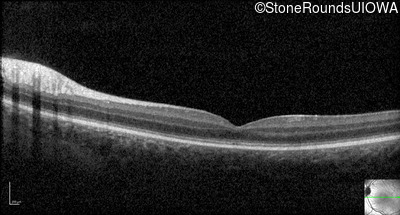

Optical Coherence Tomography - Right - 10/100

Exemplar / OCT Stack

Optical Coherence Tomography - Left - 10/100